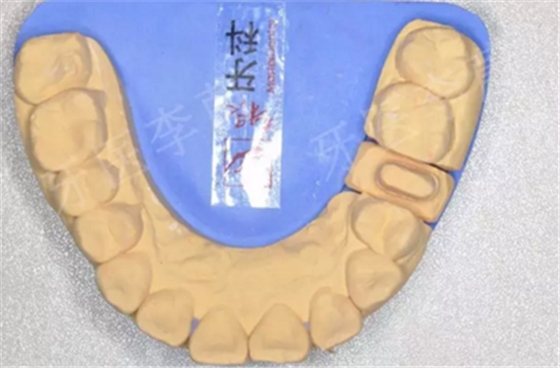

15牙樁核模型